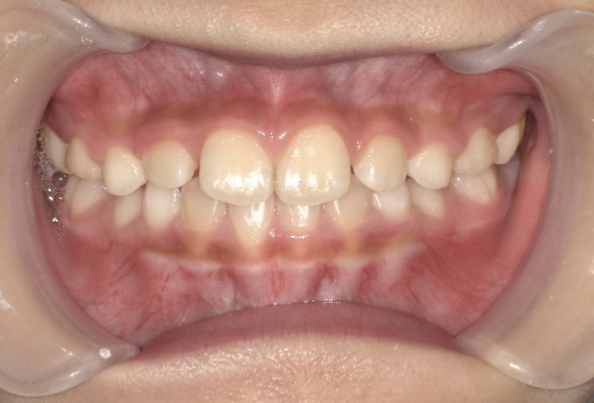

お子さんが「矯正治療」をはじめる時に直面する問題は 「装置が目立つ」、 そして「歯を抜く」ことがあげられます。

10歳を超えてからの治療開始ではそのようにならざるを得ないことが多いのです。

しかしながら、5〜7歳頃に治療をスタートすれば 目立ちにくい装置で、歯を抜かずに治療できることがあります。

また5〜7歳頃から治療を開始すると、骨格を改善することが可能です。

骨格が改善されるとお顔つきが良くなることが期待できます。

このように低年齢で矯正治療をスタートすることで得られるメリットがたくさんあります。

10歳を過ぎてからの矯正治療の場合、大人の歯を抜いて治療することが多くなります。 一方、下の前歯が生えてくる5〜7歳頃から治療を始めると、大人の歯を抜かずに治療することが可能です。 抜かずに治療するには早期に治療を開始することが大切です。

歯並びが悪いのは、あごの骨が成長不足で小さいことで起こります。 当院で行なっているこどもの歯ならび治療はあごの骨に働きかけることができます。 骨に働きかけることで成長不足のお子さんの骨が成長して、顔つきが良い方向に変わっていく可能性があります。 実は大きくなってからの矯正治療は歯が並んでいるだけで骨やお顔つきは変わっていないのです。 5〜7歳ぐらいで治療を開始すると成長不足の骨に働きかけて、より良い顔つきになれる可能性があります。